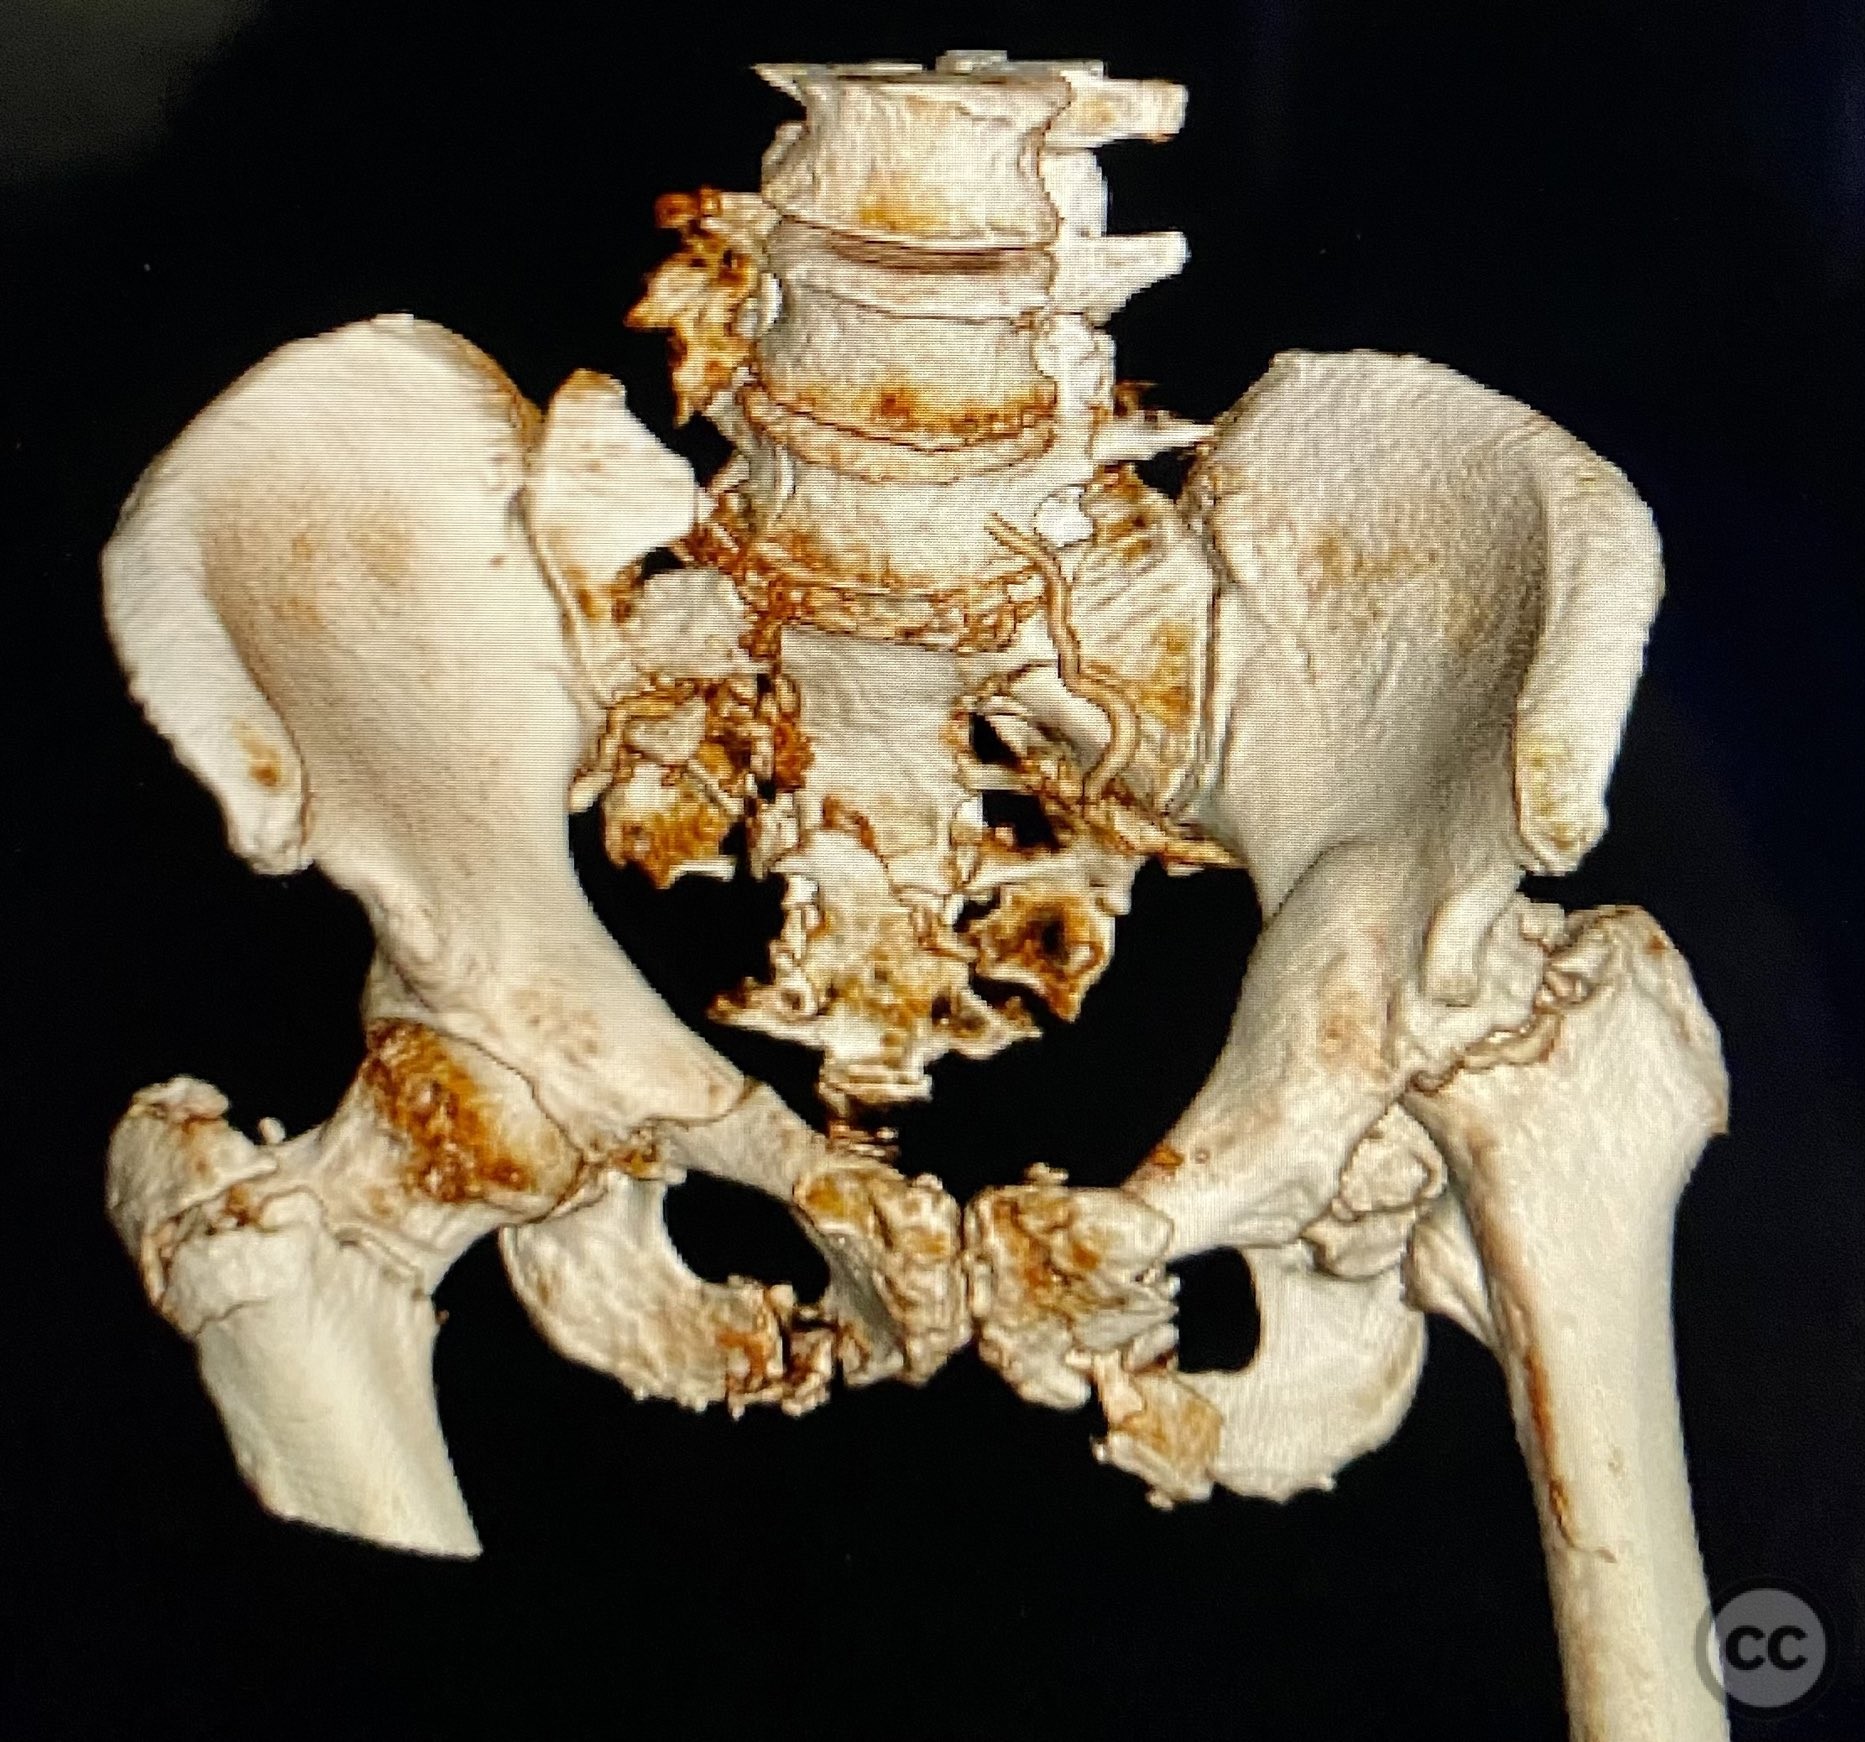

Clinical and radiological findings:  An elderly patient sustained multiple traumatic injuries, including complex unstable pelvic ring disruption (AO/OTA 61-C, likely C1 or C2 based on instability and comminution), comminuted proximal femoral fracture (AO/OTA 31-A3 or 31-B, depending on trochanteric or neck involvement), and significant abdominal trauma necessitating intra-abdominal packing. Initial clinical evaluation revealed hemodynamic instability and poor bone quality consistent with advanced age. Distal femoral traction was applied for provisional reduction. Radiological assessment was limited by osteopenia, fracture comminution, and the presence of abdominal packing materials.

Anatomical surgical approach:  Percutaneous iliosacral screw fixation was performed through small lateral gluteal incisions, with blunt dissection to the outer table of the os ilium. Under fluoroscopic guidance, guidewires were advanced across the sacroiliac joint into the S1 body, followed by cannulated screw insertion. For the proximal femur, a longitudinal incision was made proximal to the greater trochanter, splitting the fascia lata and gluteus medius fibers to access the piriformis fossa. A guidewire was inserted into the medullary canal, followed by sequential reaming and insertion of an intramedullary nail.

Intraoperative imaging was challenging due to osteopenic bone, fracture comminution, and interference from abdominal packing. Accurate identification of safe osseous corridors for iliosacral screw placement required multiple fluoroscopic projections and careful attention to pelvic landmarks. Bone quality necessitated cautious screw advancement to avoid iatrogenic cortical breach. After pelvic fixation, intramedullary nailing of the proximal femur proceeded without complication. Abdominal packing was removed and laparotomy wound closed after skeletal stabilization. Early mechanical stabilization of both pelvic and femoral injuries was prioritized to optimize survivability in this multiply injured elderly patient.